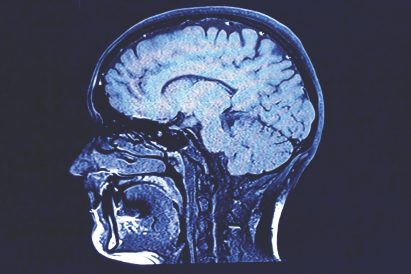

article image - MetroCreative

Doctors at both facilities connect via video monitor and are able to share CT (computed tomography) scan images to see inside a stroke patient’s brain. That helps the team decide whether to administer clot-busting medicines or if another type of procedure is needed.